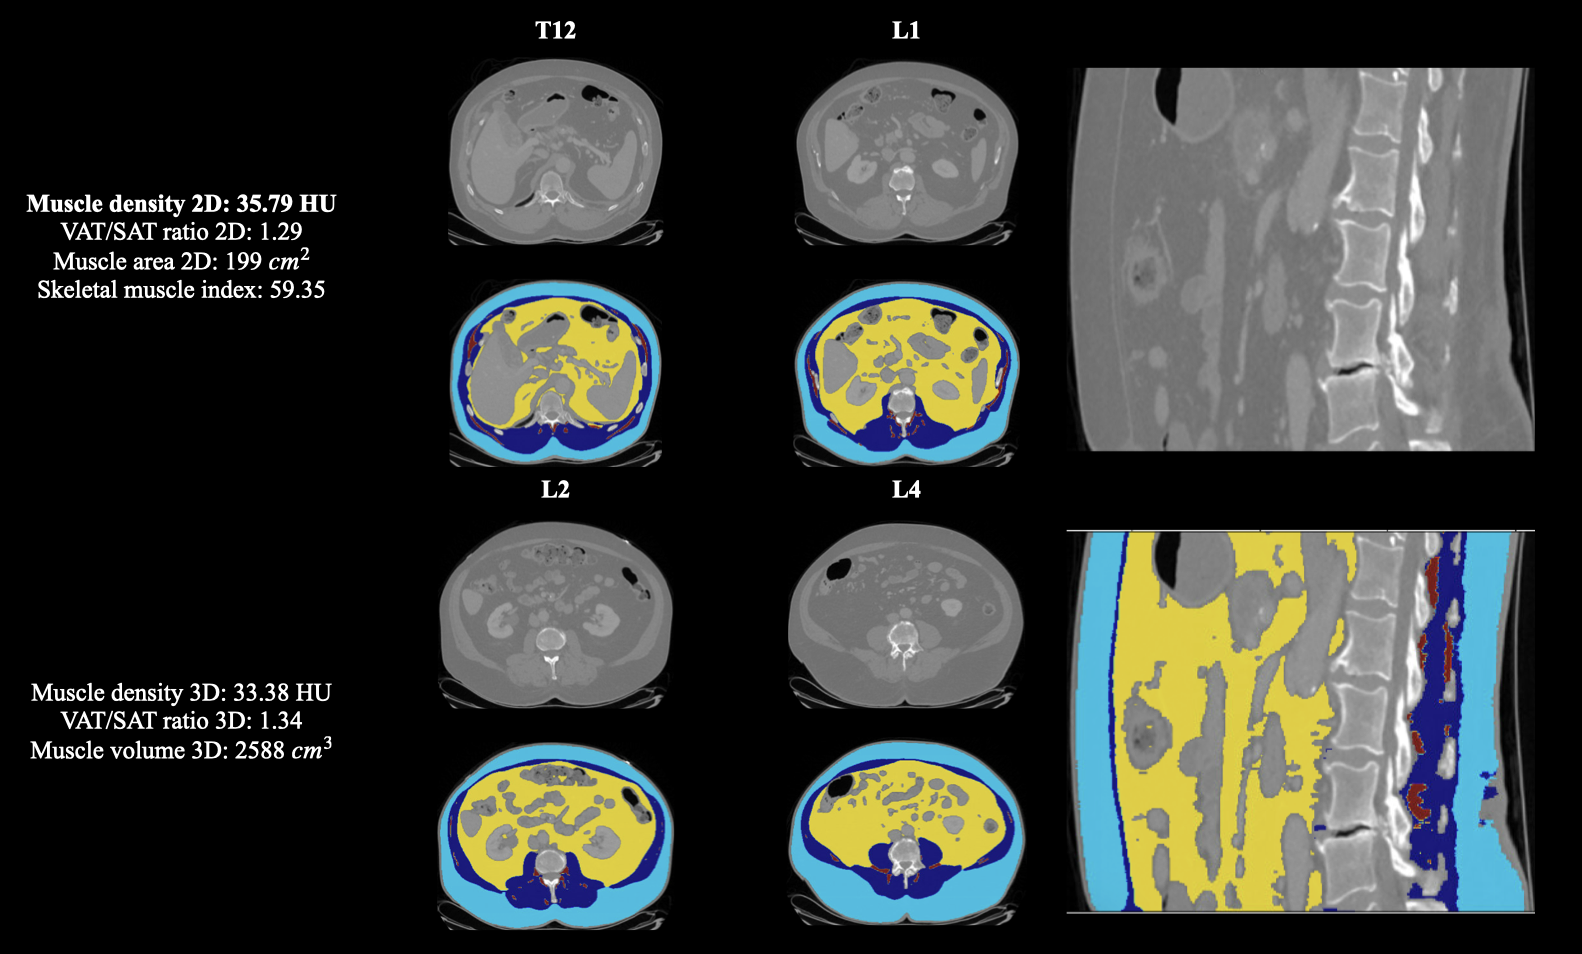

We provide end-to-end standardized and publicly available measurements for four common body composition metrics, including muscle density, visceral-to-subcutaneous fat (VAT/SAT) ratio, muscle area/volume, and SMI on both L3 for 2D and T12 to L4 for 3D measurement.

Our model is capable of measuring four commonly used body composition metrics: muscle density, VAT/SAT ratio, muscle area/volume, and SMI in both 2D and 3D settings. The detailed descriptions for these four body composition including their calculation methods, clinical significance, and associations with diseases are summarized in Table 7 in Appendix C. By analyzing previous studies on body composition analysis, we selected the third lumbar vertebral level (L3) for 2D body composition measurements and the region spanning the twelfth thoracic vertebral level (T12) to the fourth lumbar vertebral level (L4) for 3D measurements. L3 is considered the most commonly used standard for body composition assessment in multiple clinical applications, including rectal cancer assessment (Han et al., 2020; Arayne et al., 2023), sarcopenia evaluation (Amini et al., 2019; Pickhardt et al., 2020b, a), and obesity research (Liu et al., 2023; Malietzis et al., 2015). For the 3D body composition measurement, T12 is selected as the beginning of the 3D measurement region following the approach of previous studies (Demerath et al., 2007; Tong et al., 2014). This focus is particularly relevant for assessing visceral adipose tissue (VAT) and subcutaneous adipose tissue (SAT); however, recent studies related to sarcopenia and rectal cancer also pay increasing attention to T12 (Fernández-Jiménez et al., 2024; Arayne et al., 2023; Soh et al., 2024). L4 is selected as the ending point since 92.62% of our internal abdominal CT volumes include L4, while only 78.07% include L5.

Fig. 2 demonstrates the L3 segmentation results and their corresponding body composition metrics (muscle density, VAT/SAT ratio, muscle area/volume, and SMI) for five selected patients. These examples were carefully selected to reflect extreme variations in body composition within the Demographic Analysis dataset, including exceptionally low and high values of muscle density (Patient 3 and Patient 2, respectively), VAT/SAT ratio (Patient 2/5 and Patient 4), muscle area (Patient 1 and Patient 2), and SMI (Patient 1 and Patient 5).

For a more comprehensive qualitative evaluation across patients with varying body composition levels, including all four metrics in both 2D and 3D visualizations, the figures are presented in Appendix E.

5.3.3 Analysis metric evaluation

For the metric evaluation, we utilize our auto-segmentation to measure four selected body composition metrics: muscle density, VAT/SAT ratio, muscle volume, and SMI, in both 2D and 3D settings on our internal test dataset. These results are compared with the body composition metrics derived from manual annotations. The MRAE result is presented in Table 4.

The model demonstrates the best performance in measuring muscle density among four body compositions, with an MRAE lower than 5% on both internal and external datasets for both 2D and 3D measurements. Across all body composition metrics for both datasets, the model achieves an MRAE lower than 10%, showcasing its robustness.